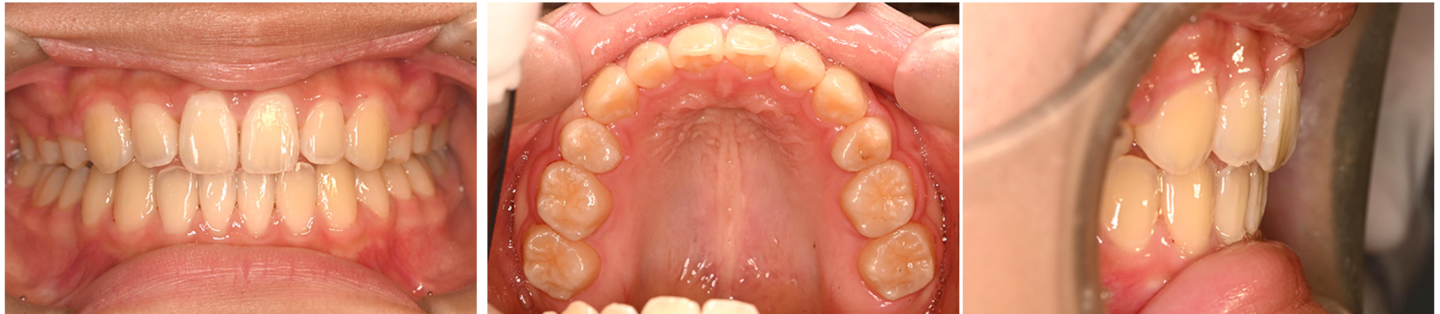

37歳男性 歯列不正 上下小臼歯抜歯 マウスピース矯正

治療前の写真

治療前

治療後の写真

治療後